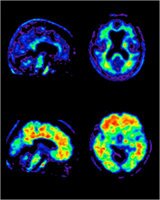

Positron emission tomography could provide early detection of Alzheimer’s

New York Times : Once a cure for Alzheimer’s has been found and tested, doctors will need a way to identify patients who can benefit from the cure before brain damage becomes too severe. Gina Kolata of the New York Times reports on a promising new technique for early Alzheimer’s diagnosis. The technique relies on standard positron emission tomography. What’s new is the development of a radioactive tracer that reliably binds to the amyloid plaques in the brains of Alzheimer’s patients.